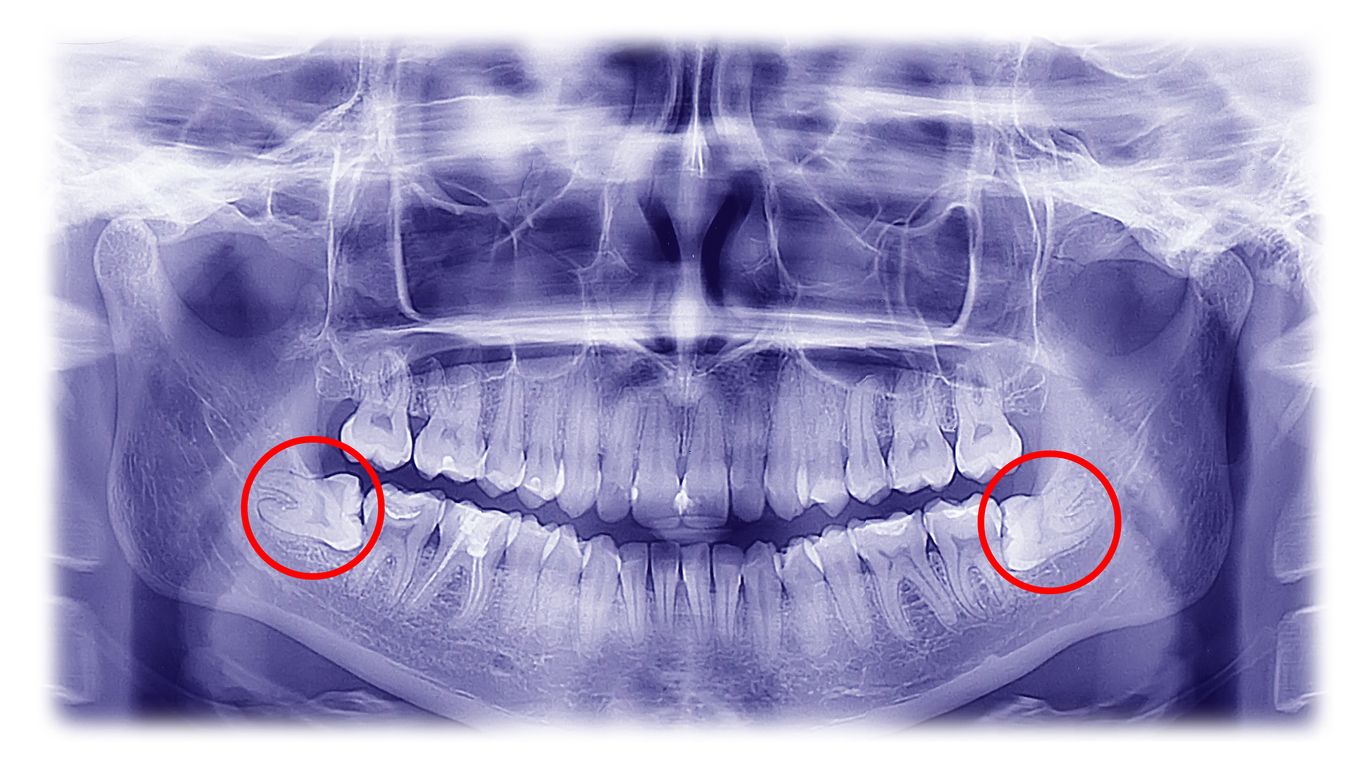

Cordales inflamadas

Muelas del juicio con dolor, inflamación o dificultad para abrir la boca.